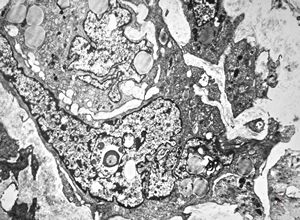

F,25y. | myopathy - atrophic and regenerating muscle cells

M,2y. | myopathy - regenerating muscle cell